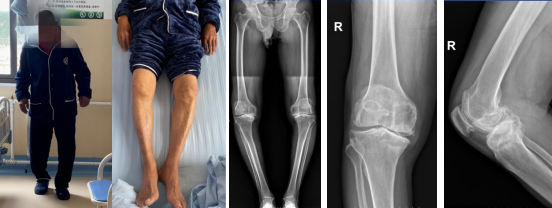

“医生,我父亲年纪大了走不动,能帮他看下片子吗?”当哈尼(化名)带着步履蹒跚的老父亲哈辛(化名)找到迪庆藏族自治州人民医院坐诊的骨科吴传龙医生的时候,吴医生发现哈辛老伯双腿弯曲,行走困难。仔细询问,原来老伯哈辛在10年前被诊断为双膝骨关节炎,尽管一直靠药物维持,但膝关节症状一直在进展,右腿甚至逐渐变形,难以行走,由于医疗条件限制,从前健步如飞的他只能卧床靠子女照顾。

但“组团式”援滇医疗团队的到来,使哈辛免于舟车劳顿之苦,在“家门口”的医院便可以实施大手术。术前检查评估提示,哈辛老伯的双侧膝关节重度屈曲挛缩和骨缺损。考虑老伯年龄较大,手术难度较高,吴医生与瑞金总院关节外科专家何川教授进行“零距离”视频查房沟通后,将手术分为两期进行,本次行右全膝关节置换术,3个月后进行左侧手术。

7月中旬,由骨科吴传龙医生主刀的右全膝关节置换术手术圆满完成,共耗时1个多小时,术后第二天,老伯便在康复团队帮助下,下床进行负重行走锻炼,他激动地说:“吴医生,3个月后不见不散,明年我又能上山采松茸啦!”